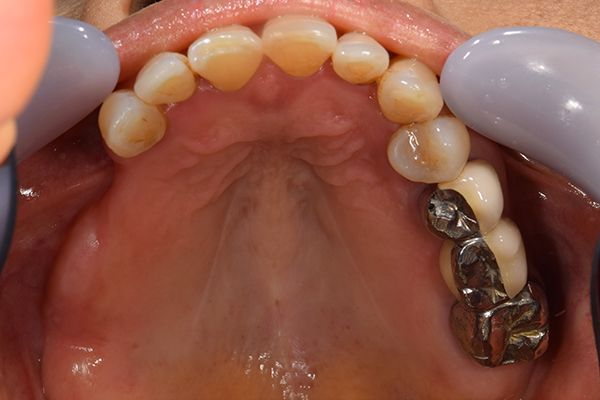

ケース1(自費の部分入れ歯)

前歯が折れて当院にいらっしゃいました。 過去に下の入れ歯を作ったが、合わなくなってずっと入れ歯をいれていらっしゃらない患者様でした。 これは奥歯で噛むことができないため、前歯で噛むことを繰り返したために、負担に耐えられなくなった前歯が折れてかぶせ物ごと 外れてしまったのだと考えられます。 痛くない、違和感の少ない、下の入れ歯を作ることがこの方のゴールであると考えられました。

シリコンで精密な型取りを行いました。

噛み合わせチェックです。 奥歯でしっかりものが噛める様に高さを決めていきました。

金属を使用して、薄く違和感が少ない入れ歯が完成しました。 また、見た目にも気を使い、バネが見えにくい様な構造にしました。

入れ歯をお口の中にいれた状態です。前歯もMTMといって、歯を少し引っ張り出す処置を行なったことで、しっかり残せて、またかぶせ物をしました。

年齢 70歳・女性

主訴 前歯が取れた

治療期間 8ヶ月

治療費 .MTM:110,000円

.ファイバーコア:16,500円

.E-maxクラウン:110,000円

.義歯:660,000円

治療方針 長年使ってきた義歯の人工歯が磨耗し、臼歯部での咬合がすくなくなり、前歯部での接触が強くなったことで生じた前歯の破折なので、義歯も作り変える必要がある。

治療内容 前歯部MTMと同時に審美面の回復。

MTM中に義歯の作成も同時に行う。

最終的に義歯と前歯のクラウンを同時にいれる。

義歯は下顎で、しっかり噛めること、違和感の少ないものという希望があったため、なるべく入れ歯を薄く作成するために金属をしようした義歯とした。

また、見た目もあまり義歯が目立たない様に、バネの部分を見えにくいように作成した。

特記事項 歯にもともと入っていた金属の種類によっては、歯自体の変色を治療で変えられないこともある。 義歯は作ってから痛みがでることがありますが、それは調整を行うことで痛くなくすることができます。